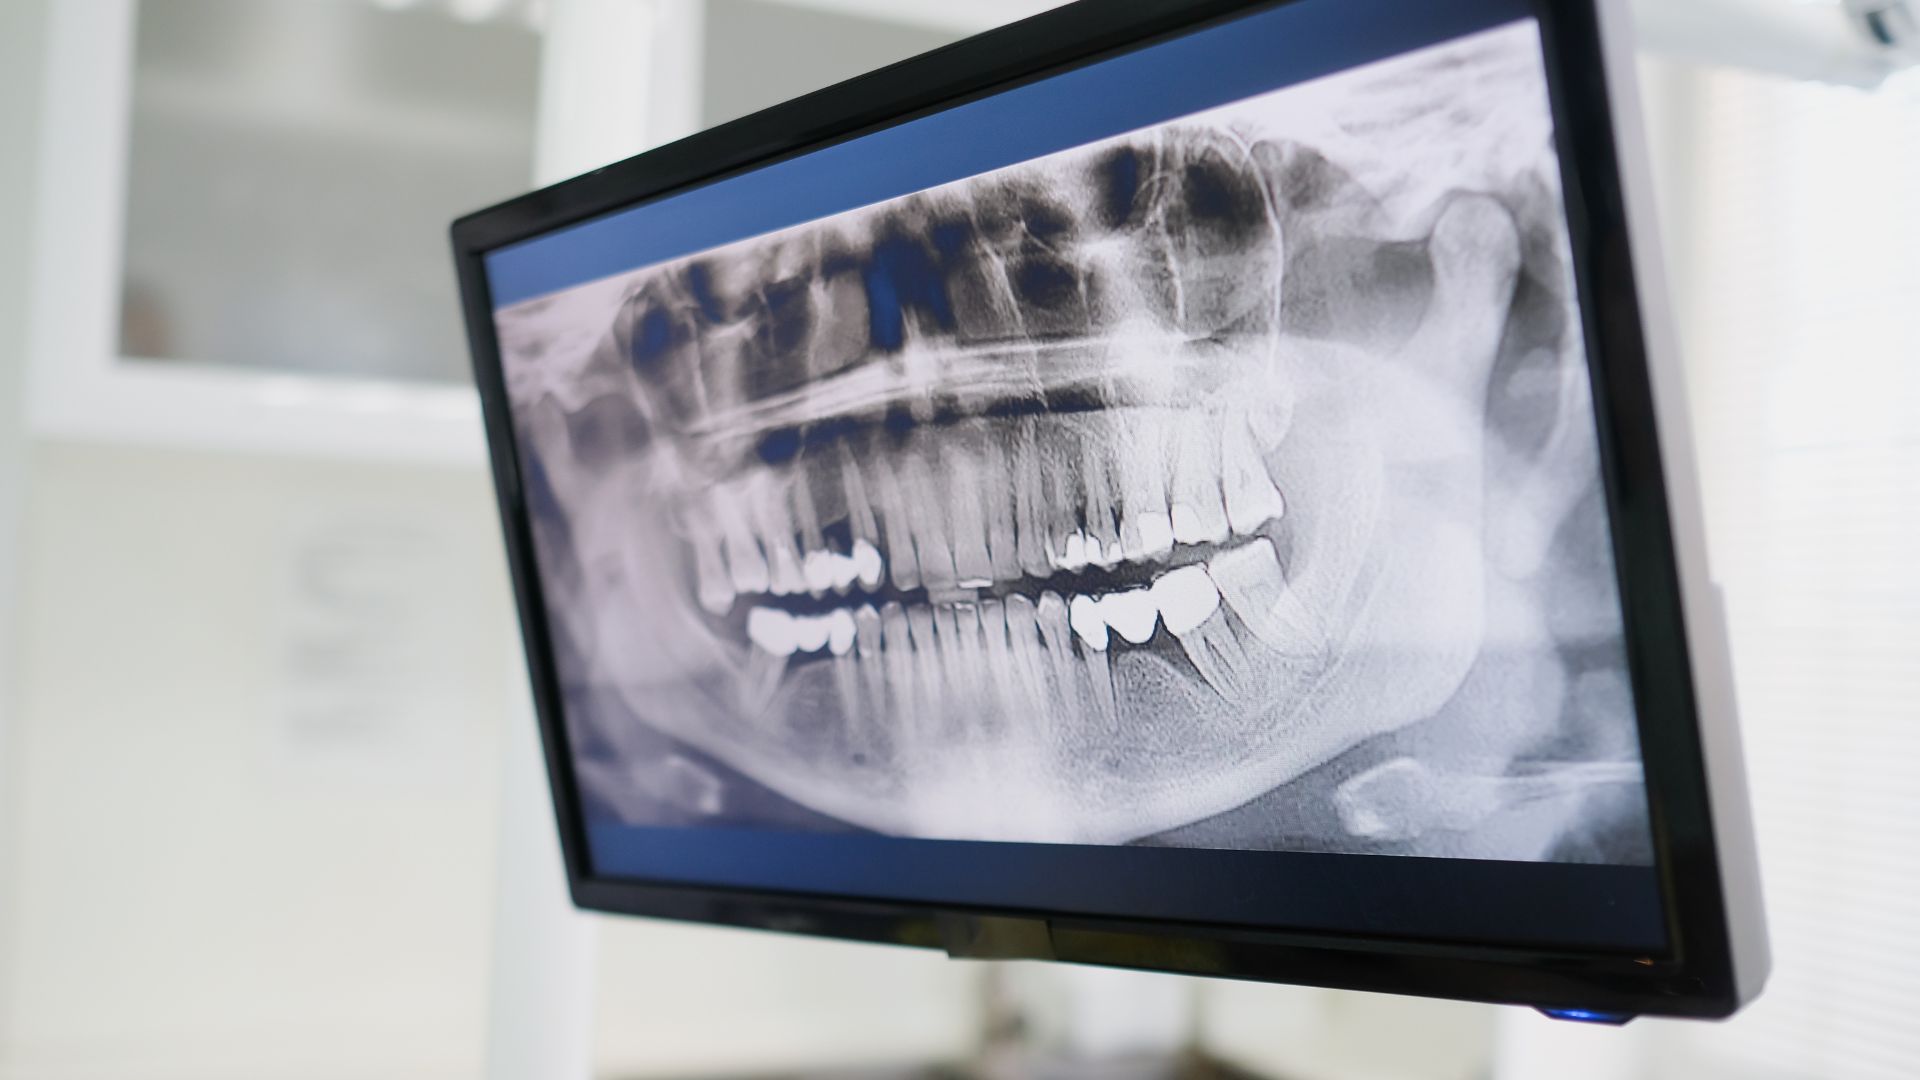

- Chụp X-quang hàm: Bạn ngồi yên trên ghế, nha sĩ dùng máy X-quang để chụp hình xương hàm, mất 5 phút. Phương pháp này kiểm tra xem xương có bị mất đi không, đặc biệt với tụt lợi nặng, và rất an toàn nếu đội áo chì.